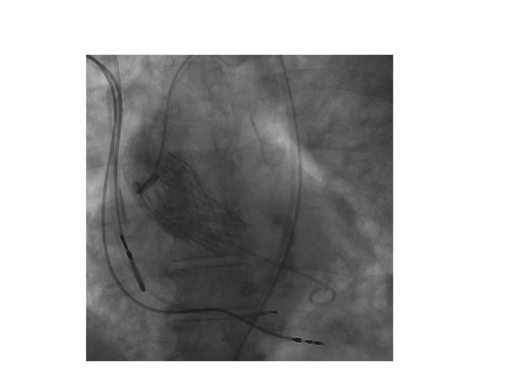

Eine hochgradige Stenose der Aortenklappe kann seit einigen Jahren auch katheterinterventionell behandelt werden. Dabei kann die neue Herzklappe über die Leistenarterie, über die Herzspitze oder über andere Zugangswege implantiert werden. Der entscheidende Vorteil liegt darin, dass dieser Eingriff weniger invasiv als eine konventionelle Operation an der Aortenklappe ist und entsprechend vor allem für jene Patienten in Frage kommt, bei denen aufgrund des Alters oder von Begleiterkrankungen ein zu hohes Risiko für eine konventionelle Operation besteht. Die Mehrzahl der Eingriffe wird ohne Vollnarkose durchgeführt. Bei der minimalinvasiven Aortenklappen-OP (TAVI = transcatheter aortic valve implantation) werden sämtliche Instrumente über Drähte und Katheter zum Herzen vorgebracht. Im Gegensatz zur Operation, bei welcher die alte Klappe durch eine neue Herzklappe ersetzt wird, wird bei der TAVI-Methode die neue Herzklappe durch Aufblasen eines Ballons über die alte Klappe platziert. Diese wird dabei vollständig gegen die Wand gedrückt und die neue Klappe übernimmt ihre Funktion nach Ablassen des Ballons.

An der Uniklinik RWTH Aachen wurden mittlerweile weit über 1.000 Patienten mit der TAVI-Methode versorgt. Alle Patienten werden von einem spezialisierten Team aus Kardiologen, Herzchirurgen und Anästhesisten vorab in einer gemeinsamen Herz-Team-Besprechung ausführlich besprochen, um zu überprüfen, mit welcher Prozedur für den individuellen Patienten das beste Ergebnis zu erwarten ist. Als Zugangswege kommen der transfemorale, transaortale, transapikale (Herzspitze) oder ein Zugang über die Schulterarterie (A. subclavia) infrage. Der Eingriff wird im gemeinsam von erfahrenen Oberärzten der Kardiologie und der Herzchirurgie durchgeführt, so dass für jeden Patienten die höchstmögliche Sicherheit gewährleistet ist. Nach dem Eingriff kommen die Patienten, meist bereits in wachem Zustand, für eine Nacht auf eine Überwachungsstation. Der gesamte Klinikaufenthalt liegt bei unkompliziertem Verlauf bei drei bis vier Tagen.